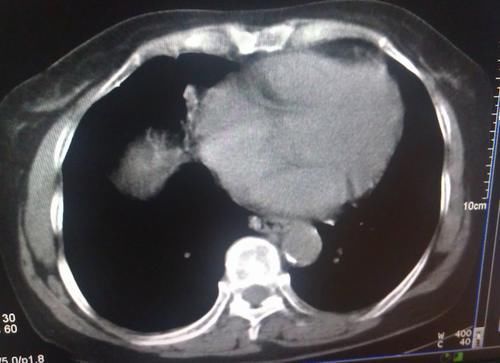

说到肺癌,就不得不提到肺结节,肺癌早期病变,通常会是以结节的形式展现,肺结节在肺CT上表现为结节疙瘩,有磨玻璃结节、有实性结节,还有混合磨玻璃结节。

文章插图

长沙市中心医院的刘剑波主任认为,肺结节患者能不能吃辣椒,还要分情况来对待。如果是是因为纤维化或慢性炎症导致的肺结节, 吃辣椒不会导致这种结节的变化,因为这种结节性质非常的稳定。但是,如果是炎症、肺部发炎引起的毛玻璃肺结节,此时吃一些辛辣的食物,会加剧炎症反应,降低机体免疫,从而加重结节病症。